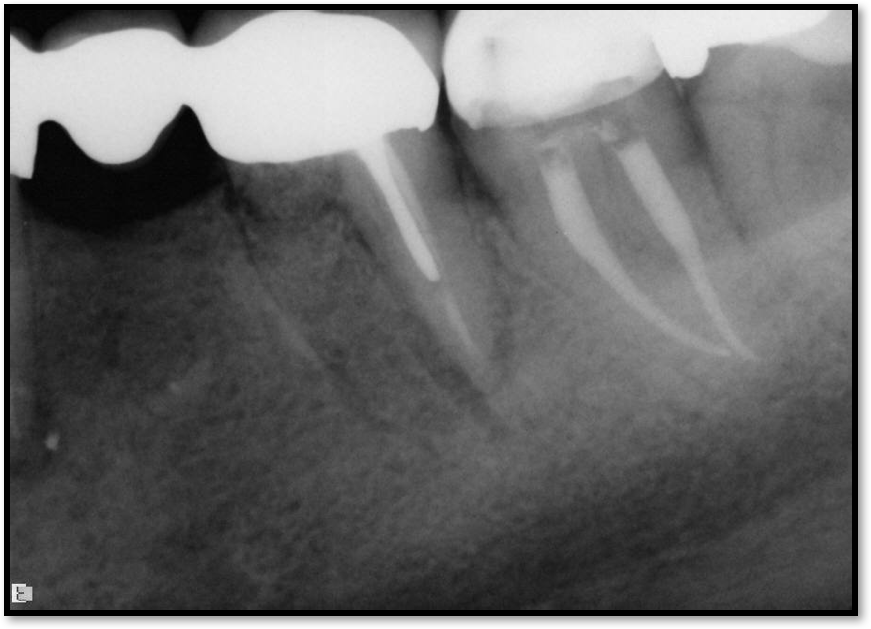

Fig 13. A good root canal may have been absorbed.

Figure 13

Figure 13 shows an example where there was likely a good root canal that was absorbed. The way to avoid this type of problem is that the person who does the root canal should do the post. This is not always possible, and some general dentists like to do the restorative work themselves, but the advantage of having the same person do both is that the person is familiar with the curve of that canal. That clinician also knows the thickness of the walls and what the canal will allow. In this case, it was done under a rubber dam, which was beneficial; often clinicians will see teeth that have good endodontics, but multiple years later, radiolucency will appear because when the post was placed, saliva seeped in.